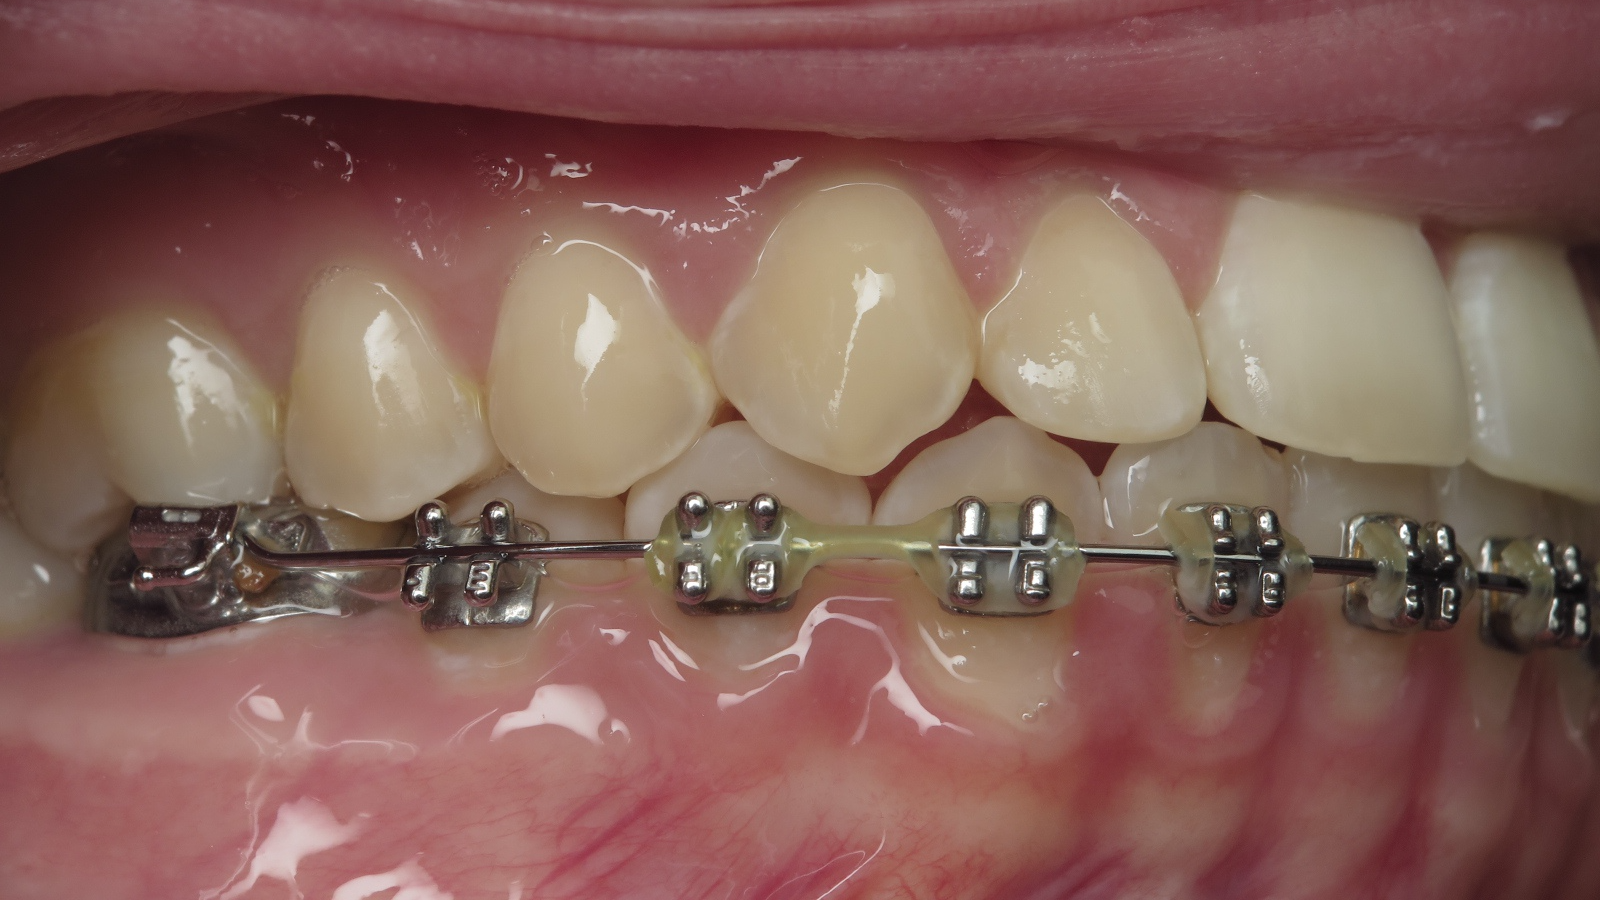

appareillage multibagues traitement en cours

bilan début et en cours de traitement